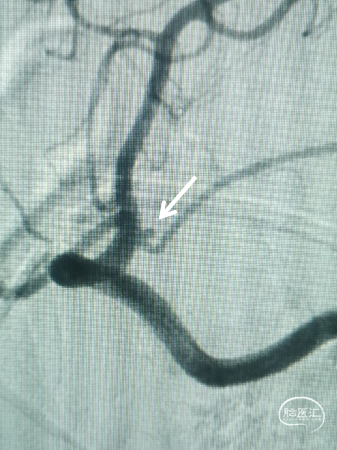

术前造影

左侧脉络膜前动脉起始部微小动脉瘤,约1.3mm*0.9mm,载瘤动脉远端3.7mm,近端4.2mm;右侧后交通动脉起始部微小动脉瘤,约2.3mm*1.7mm,载瘤动脉远端3.8mm,近端4.1mm。

LICA

RICA

术中诊断:左侧脉络膜前微小动脉瘤(责任);右侧后交通微小动脉瘤。